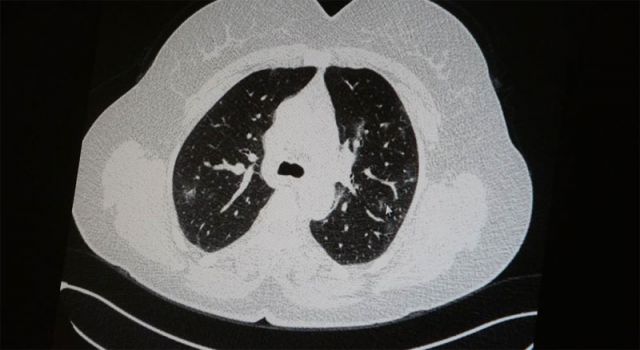

Genç olduğu halde aşı olmayanlarda hastalığın ağır seyrettiğini ifade eden Uzm. Dr. Azar, "Ben gencim, benim bağışıklık sistemim kuvvetli" diyen genç bir hastanın akciğerlerinde ciddi lekelenmelerin olduğunu ve korona virüs zatürresi olduğunu gördüklerini belirtti.

Uzm. Dr. Azar, aynı şekilde aşı olup korona virüs hastalığına yakalanan bir başka genç hastanın akciğer tomografisinde akciğerde herhangi bir sorunun olmadığını ve hastanın durumunun iyi olduğunu gözlemlediklerini kaydetti. Uzm. Dr. Azar, sürekli şahit oldukları "Keşke biz aşı olsaydık" sözünü bir daha duymamak için herkesi aşı olmaya davet etti.